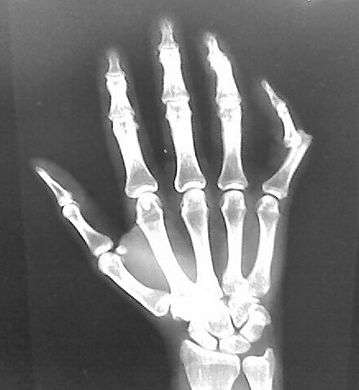

X-rays are usually taken to confirm a diagnosis and detect any fractures which may also have occurred at the time of dislocation. A dislocation is easily seen on an X-ray.[8]

Gallery

Dislocation of the left index finger

Radiograph of right fifth phalanx bone dislocation- Radiograph of left index finger dislocation